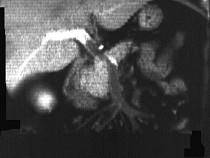

问题 男性,40岁,半年前因双下肢麻木、发凉、疼痛于外院诊断血栓闭塞性脉管炎,近1周腹痛、腹胀,以中下腹为著,呈阵发性加剧就诊,行CT增强扫描,如图所示 ( )

选项 A.胰头部略膨隆,内部密度不均。 B.门静脉及肠系膜肠系膜上静脉增宽。 C.门静脉及肠系膜静脉内见条形充盈缺损。 D.考虑为胰头癌。 E.考虑为门静脉及肠系膜内血栓形成。

答案 ABCE